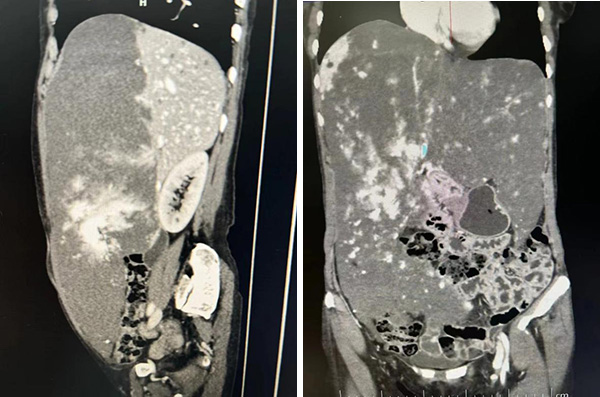

收入住院后,朱主任和魏林主任迅速给张女士设计了周密的术前评估计划。从影像学检查上可以看到,患者肝内重要的血管和胆道都被肿瘤所紧密包绕,在体如果有损伤会非常被动,如果离体切除肿瘤,修补和重建管道的难度会大大减小,安全性会提高。同时,张女士有短时间内肿瘤迅速生长的病史,需要与恶性疾病鉴别诊断。其次,张女士的肿瘤切除后,剩余肝脏是否够用,是否会发生肝衰竭,还需要估测肿瘤和残余健康肝脏的体积。

肝移植中心鲁一达医师估测了肿瘤和残肝的体积,此时的肿瘤已经生长到了9.5厘米x23.6厘米x31.5厘米,体积达5400立方厘米,而残余的健康右半肝仅有800立方厘米。为此,肝移植中心组织影像中心、肝病内科和肿瘤科专家进行MDT (多学科诊疗团队)会诊,张女士的病情得到了全面评估。